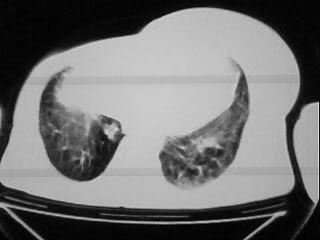

以下是引用随光逐影在2009-2-10 0:07:00的发言:[br]1)右肺放射性肺炎并节段性肺不张?请结合相关病史。2)右侧胸膜肥厚、粘连。3)心包膜增厚(或心包少量积液)。